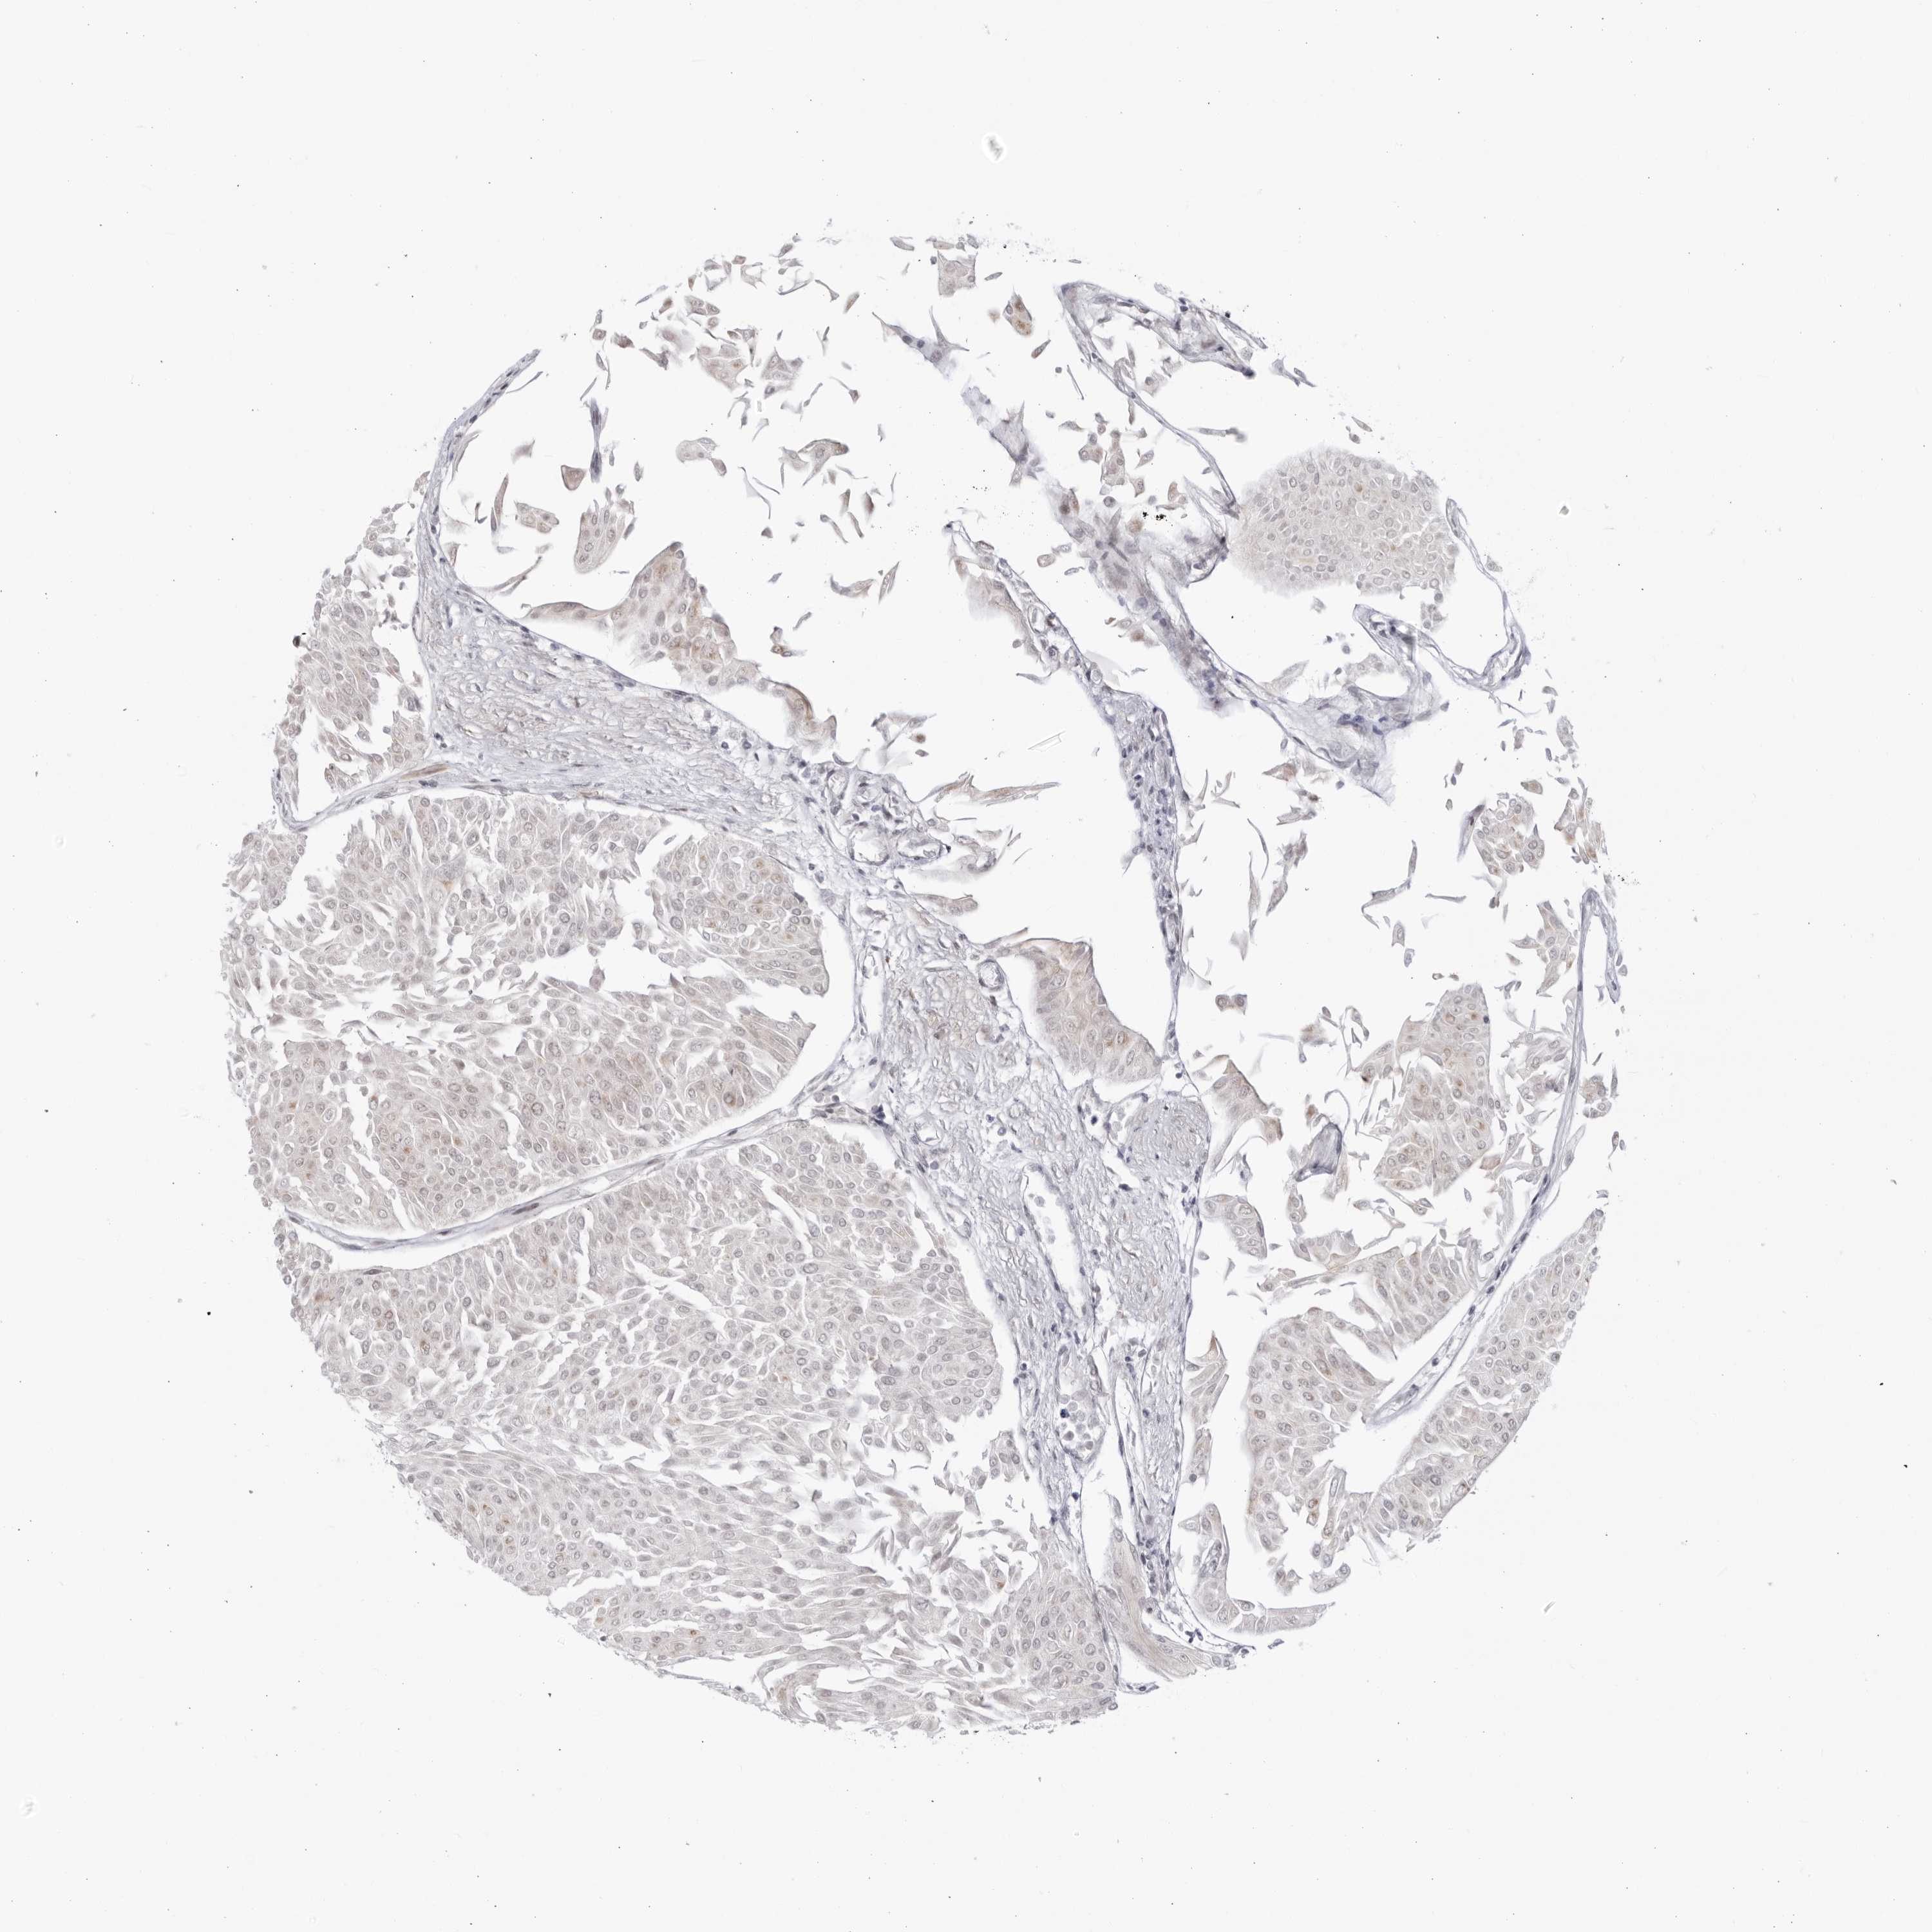

UROTHELIAL CANCER - Protein expressioni

A mouse-over function shows sample information and annotation data. Click on an image to view it in a full screen mode. Samples can be filtered based on level of antibody staining by selecting one or several of the following categories: high, medium, low and not detected. The assay and annotation is described here.

Antibody stainingi

Antibody staining in the annotated cell types in the current human tissue is reported as not detected, low, medium, or high, based on conventional immunohistochemistry profiling in selected tissues. This score is based on the combination of the staining intensity and fraction of stained cells.

Each image is clickable and will lead to virtual microscopy that enables deeper exploration of all samples and also displays staining intensity scores, fraction scores and subcellular localization as well as patient and tissue information for each sample.

Antibody HPA028016

Staining

High

Medium

Low

Not detected

Intensity

Strong

Moderate

Weak

Negative

Quantity

>75%

75%-25%

<25%

None

Location

Nuclear

Cytoplasmic/membranous

Cytoplasmic/membranous,nuclear

Urothelial carcinoma, Low grade

Urothelial carcinoma, High grade